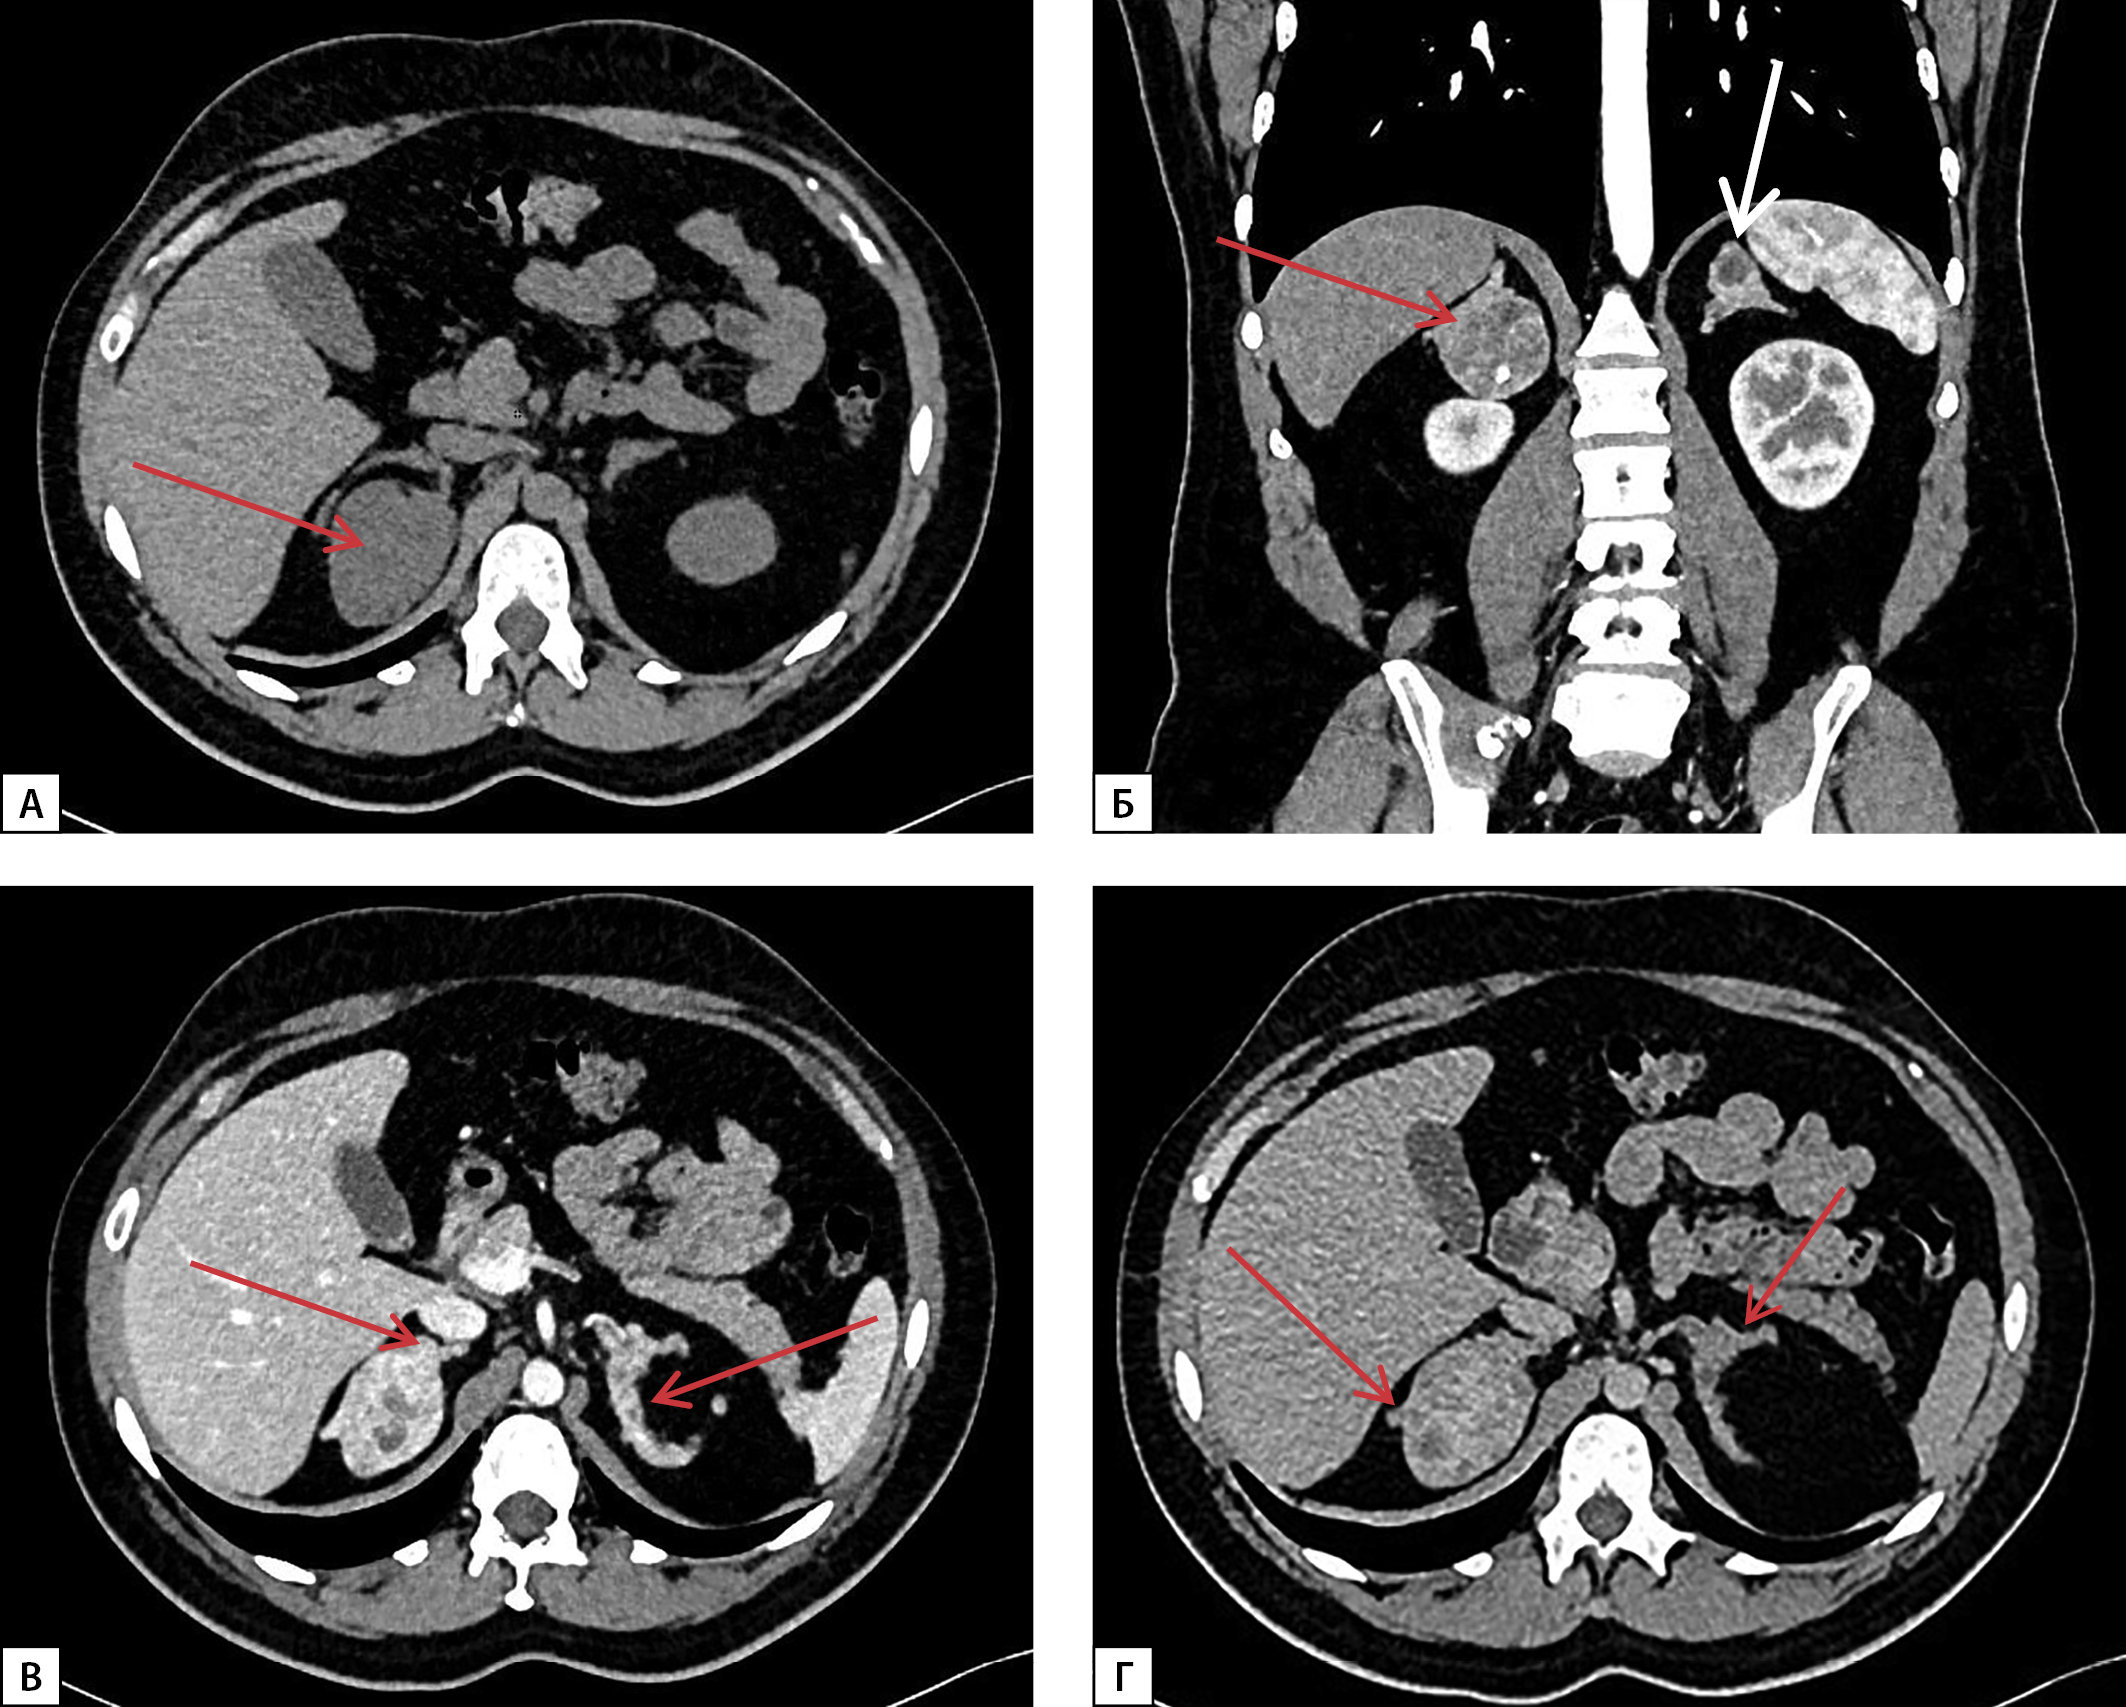

По данным МСКТ надпочечников с внутривенным контрастированием от 02.03.2022 г., левый надпочечник замещен крупным многоузловым жиросодержащим образованием размерами 26х14х17 см с наличием в структуре кальцинатов размером до 8 мм, оттесняющим вправо петли тонкой кишки, двенадцатиперстную кишку, поджелудочную железу, брыжейку тонкой кишки, верхнюю брыжеечную артерию, чревный ствол, влево — поперечный отдел ободочной кишки, селезенку, смещающим почку книзу с ротацией ворот, и с плотностью перегородок и солидного компонента по фазам: 30-45-165-60 HU (нативная — артериальная — венозная — отсроченная фазы соответственно), абсолютный коэффициент вымывания — 78%, относительный коэффициент вымывания — 63%; правый надпочечник замещен многоузловым жиросодержащим образованием размерами 7,5х4,2х6,5 см в медиальной ножке, 7,7х3,5х8,7 см в латеральной ножке, 3,5 см в теле, прилежащем к правой доле печени, плотностью по фазам сканирования 26-40-65-60 HU (нативная — артериальная — венозная — отсроченная фазы соответственно) (рис. 1).

Рисунок 1. МСКТ надпочечников с контрастным усилением:

А — нативная фаза — левый надпочечник замещен крупным многоузловым жиросодержащим образованием (белая стрелка), с перегородками, в структуре образования кальцинаты (красная стрелка); Б — артериальная фаза — образование левого надпочечника оттесняет вправо петли тонкой кишки, двенадцатиперстную кишку, поджелудочную железу, брыжейку тонкой кишки, верхнюю брыжеечную артерию, чревный ствол (красные стрелки); В — венозная фаза — правый надпочечник замещен многоузловым жиросодержащим образованием с перегородками, прилежащим к правой доле печени (красная стрелка); Г — отсроченная фаза — образование левого надпочечника смещает почку книзу с ротацией ворот, оттесняет поперечный отдел ободочной кишки, селезенку влево (красная стрелка).